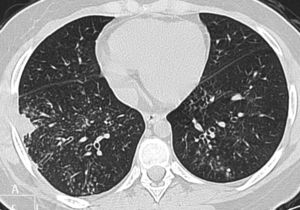

Figure 1.

An 8-year-old girl with a confirmed diagnosis of H1N1 and respiratory failure requiring non-invasive ventilation. Computed tomography scans acquired 4 days after the onset of clinical symptoms show severe and diffuse ground-glass opacities without specific distribution in the lungs.

Initial CT was performed at a median of 5.5 days (range 4-32) after the onset of symptoms. GGO was seen in all cases (Figure 1) and was severe in three patients, moderate in four, and mild in one. The overall distribution of GGO was diffuse in five patients. In the remaining three patients, the GGO distribution was patchy. Consolidation (7/8 cases) and airspace nodules (6/8 cases) were also common findings. Consolidation was typically moderate with a diffuse and heterogeneous distribution in six patients (Figure 2) and a lobar (non-segmental) distribution in one. The extent of airspace nodules was mild in four of six cases, moderate in one case, and severe in one. The tree-in-bud pattern, interlobular septal thickening, peribronchovascular interstitial thickening, and airway wall thickening were each seen in two patients on the initial scans (Figure 3). The tree-in-bud pattern was severe in one patient and mild in another. It was most pronounced in the peripheral regions and was associated with airway wall thickening. Interlobular septal thickening was severe and diffuse in one patient, while in another, it was moderate and predominantly in the lower lobes. Peribronchovascular interstitial thickening occurred preferentially in the lower lobes and was intense in one patient and mild in another. The most frequent combination of findings was consolidation and GGO. This combination occurred in seven of eight patients and was diffuse and heterogeneous in six patients (Figure 2).

Six of eight patients (75%) developed respiratory failure and required intensive care. Prolonged H1N1 shedding was observed in the three mechanically ventilated patients, and overall hospital mortality in our series was 25%. The most frequent computed tomography findings were ground-glass opacity (all patients), consolidation (7/8 cases), and airspace nodules (6/8 cases) that were frequently moderate or severe. Other parenchymal findings were not common. Five patients had features of pneumonia, two had computed tomography findings compatible with bronchitis and/or bronchiolitis, and one had tomographic signs of chronicity.